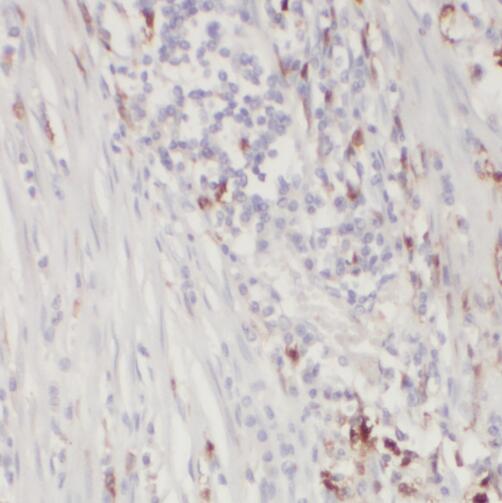

| 验证图片 | Immunohistochemistry of paraffin-embedded human colon cancer using FNab08853(TOE1 antibody) at dilution of 1:50 HeLa cells were subjected to SDS PAGE followed by western blot with FNab08853(TOE1 antibody) at dilution of 1:500 |